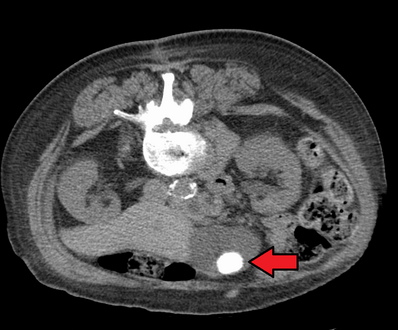

A 1.9 cm gallstone impacted in the neck of the gallbladder and leading to cholecystitis as seen on ultrasound. There is 4 mm gall bladder wall thickening.

Large gallstone as seen on CT